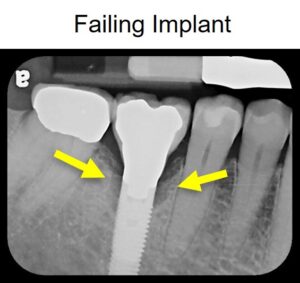

However, not every dental implant lasts (please see our previous blog, “Common Factors That Can Limit the Success of Dental Implants”). There are many reasons a patient may have an implant that is failing. A failing dental implant may cause pain, gum recession, difficulty chewing, or swelling around the restoration.

Periodontal disease, also called gum disease, can cause inflammation and infection around a dental implant (called peri-mucositis) as well as bone loss (called peri-implantitis) that can cause the implant to fail [2].

If you have gum disease that is causing a failing implant, treatment is necessary to help repair the implant site. In severe cases, the implant may need to be removed and replaced. However, mild to moderate cases of periodontal disease may only need minimal intervention in order to restore the health of the implant. In most instances, Dr. Marlin at Elite Prosthetic Dentistry can remove the abutment and crown, decontaminate the implant, and repair the implant with a bone graft.